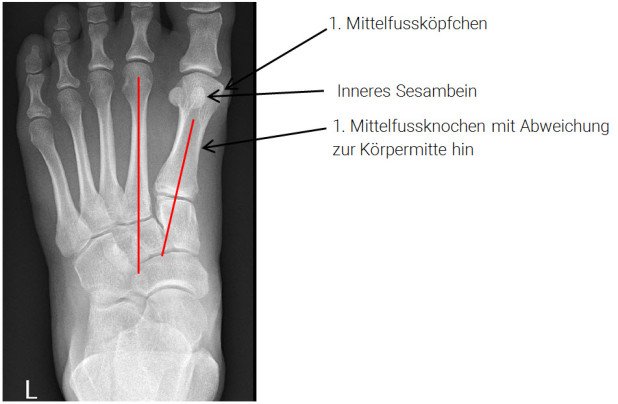

Die Röntgenaufnahmen bestätigten die Hallux-valgus-Deformität mit Abweichung des 1. Mittelfussknochens zur Körpermitte hin, wodurch das vermeintliche «Überbein» entsteht.

Die beiden Sesambeinchen verbleiben aufgrund ihrer Einbettung in den kurzen Beugesehnen und Bandverbindungen mit dem 2. Mittelfussknochen in ihrer ursprünglichen Lage, womit sich ihre Position in Relation zum 1. Mittelfussköpfchen ändert:

Der 1. Mittelfussknochen weicht zur Körpermitte hin ab, womit das 1. Mittelfussköpfchen seine Position in Relation zu den beiden Sesambeinchen ändert. Das innere Sesambein liegt jetzt zentral und damit schmerz-verursachend unter dem 1. Mittelfussköpfchen